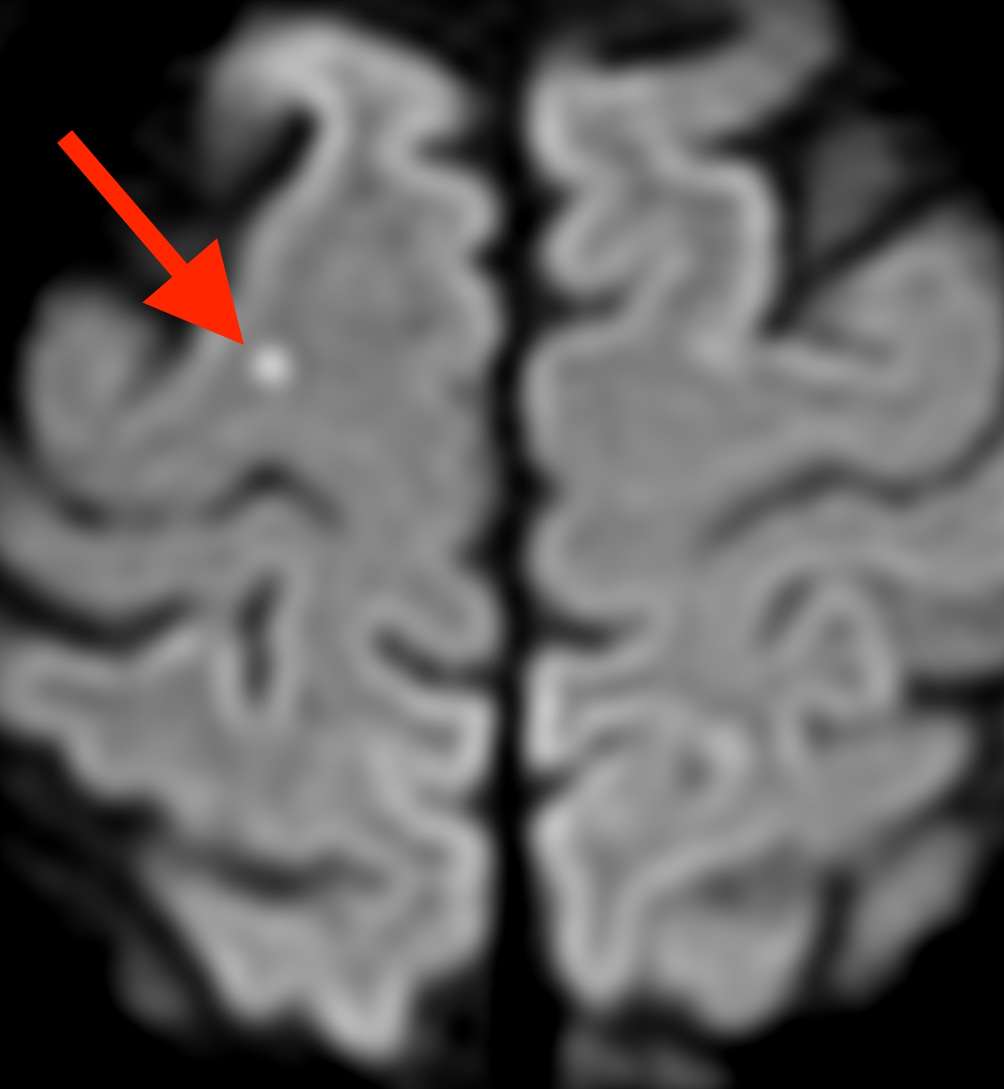

頭部MRI検査(拡散強調画像)を確認しました。

片頭痛と脳梗塞

右の前頭葉という場所に小さな脳梗塞を認めました。さらに、別々の場所に計3ヶ所の脳梗塞を認めました。小さな血栓(血液の固まり)が脳血管の複数の場所に流れ込んで生じた脳梗塞と考えられました。

片頭痛を有する方に発症した脳梗塞である事や病変の分布から、卵円孔開存が関与した脳梗塞である可能性があります。したがって、心臓を含めた詳しい検査と治療が必要です。